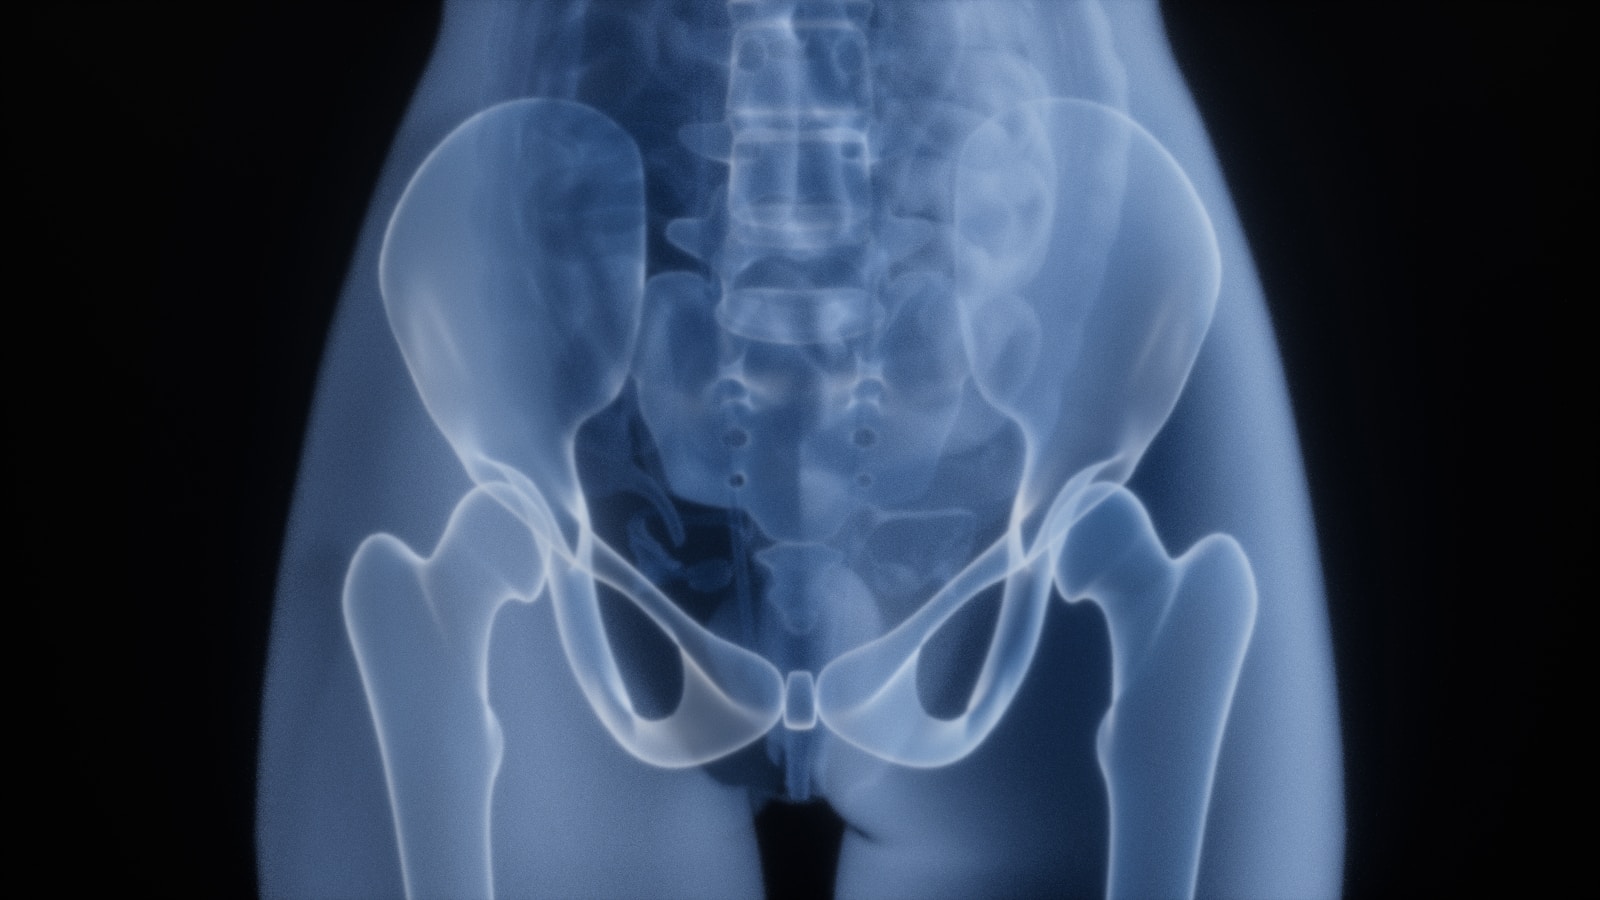

특히 걷기 습관이 무너질 때 가장 크게 흔들리는 것은 ‘골반의 안정성’이다. 사람들은 허리 통증을 허리 자체의 문제로 생각하지만, 대부분은 골반이 충분히 움직이지 못하면서 생기는 결과에 가깝다. 걷는 동안 골반은 앞뒤로 흔들리며 척추를 안정시키고, 다리와 몸통 사이의 힘을 분산한다. 그런데 걷기가 줄면 이 흔들림이 줄어들고, 골반을 잡아주는 깊은 근육들은 점점 게을러진다. 그 결과 허리는 혼자 힘으로 몸을 버텨야 하고, 무릎은 과도하게 힘을 사용하게 된다. 그래서 활동이 적은 날일수록 오히려 몸이 더 뻣뻣해지고, 작은 움직임에도 불편함이 커지는 것이다.